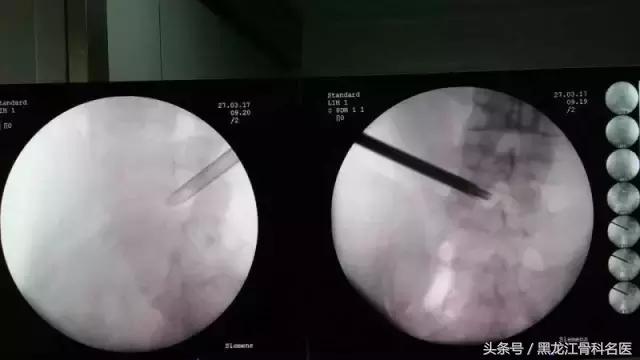

术中椎间孔镜所见

摘除突出髓核